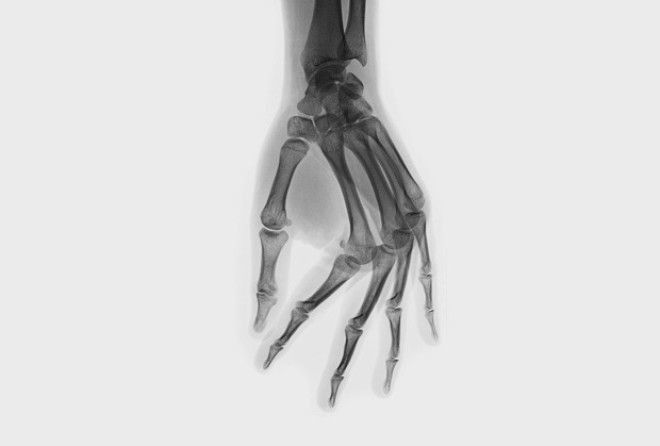

Вредно ли хрустеть костяшками?. Изображение № 2.

СУЩЕСТВУЮТ ДВЕ ГИПОТЕЗЫ, ОБЪЯСНЯЮЩИЕ ХРУСТ В СУСТАВАХ.Первая предполагает, что независимо от излюбленной техники — дёргаете ли вы палец или выкручиваете шею —происходитодно и то же: суставная капсула растягивается, её объём увеличивается, а давление, наоборот, падает. Из-за этого суставная жидкость растекается, и в ней образуются пузырьки газа. Эти пузырьки лопаются с характерным звуком. Спустя 10–20 минут газы снова растворяются в жидкости — тогда можно хрустнуть ещё раз. Согласно второй гипотезе, хруст возникает при движении из-за быстро натягивающихся связок и сухожилий. Когда капсула, сухожилия и связки растягиваются, сустав делается подвижнее, и человек чувствует комфорт. Ну а кому-то просто нравится звук.